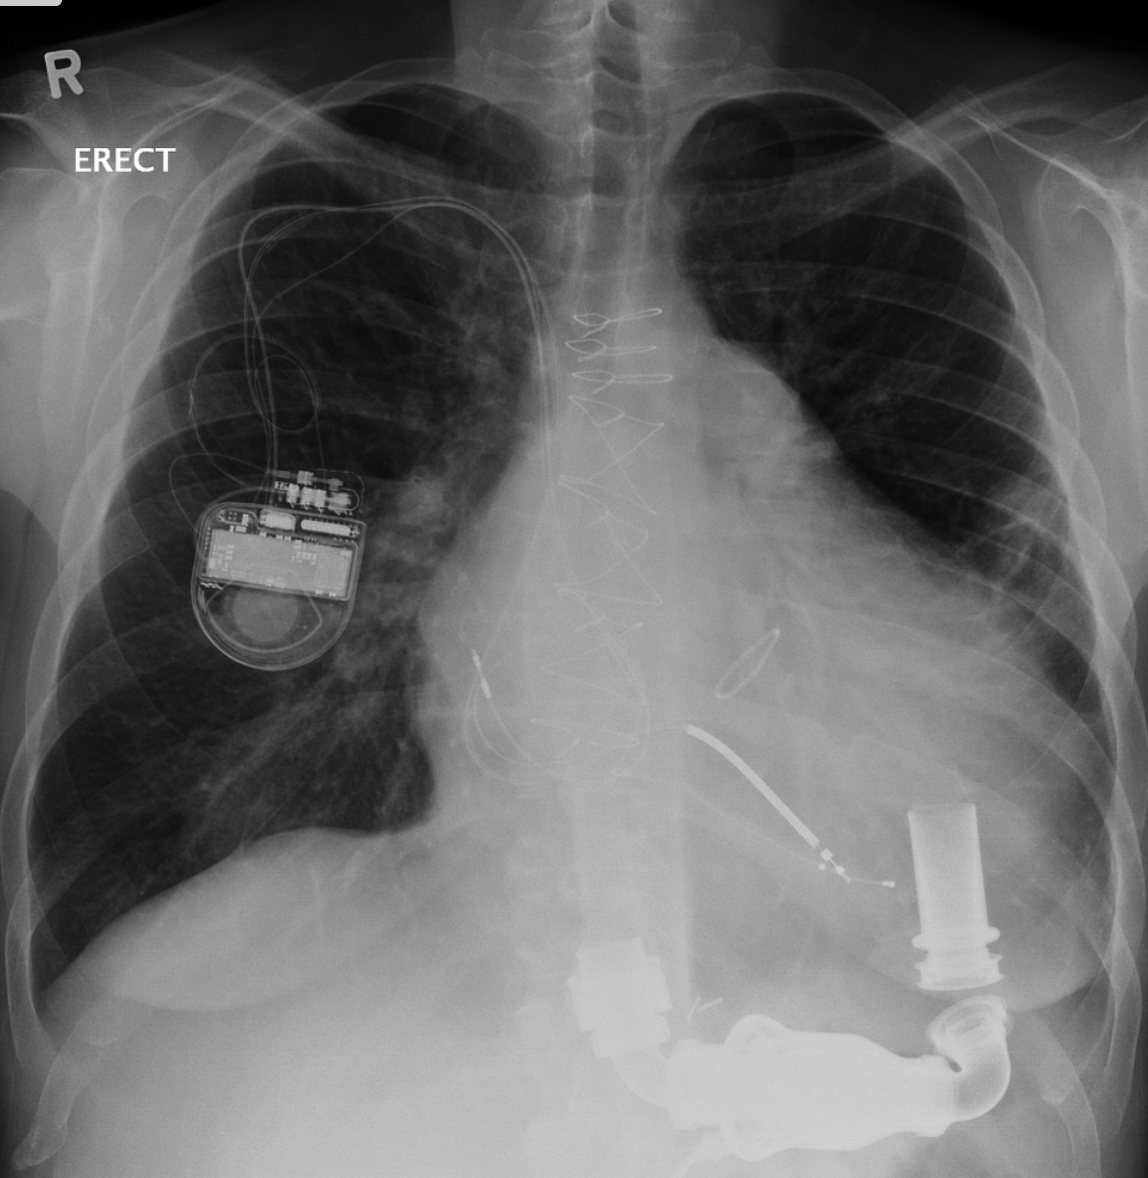

Single lead pacemaker, retracted (Twiddler)